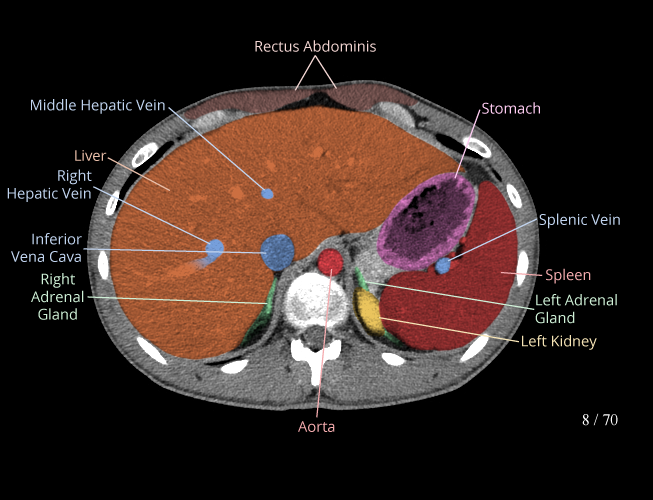

Body

Covers abdominal CT anatomy.